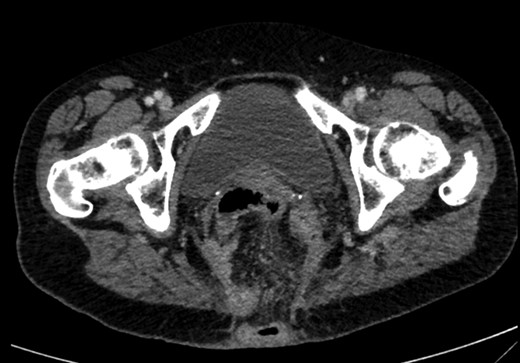

On examination, she was febrile. Her abdomen was generally tender. Bowel sounds were present and up to that time her stoma was working. Her perineal hernia was red and tender. Her initial CXR (Fig. 1) did reveal a sliver of gas underneath her right hemidiaphragm and in keeping with her abdominal findings she progressed to further imaging. CT abdomen pelvis with contrast showed pneumoperitoneum (Fig. 2) with ‘a tiny pocket of air is also seen adjacent to a loop of bowel in the pelvis posterior to the bladder’. ‘Exact site of perforation has not been demonstrated but could possibly be in the bowel loops in the perineum’ (Figs 3 and 4).

CT showing small bowel loops in pelvis with perineal hernia and free fluid.